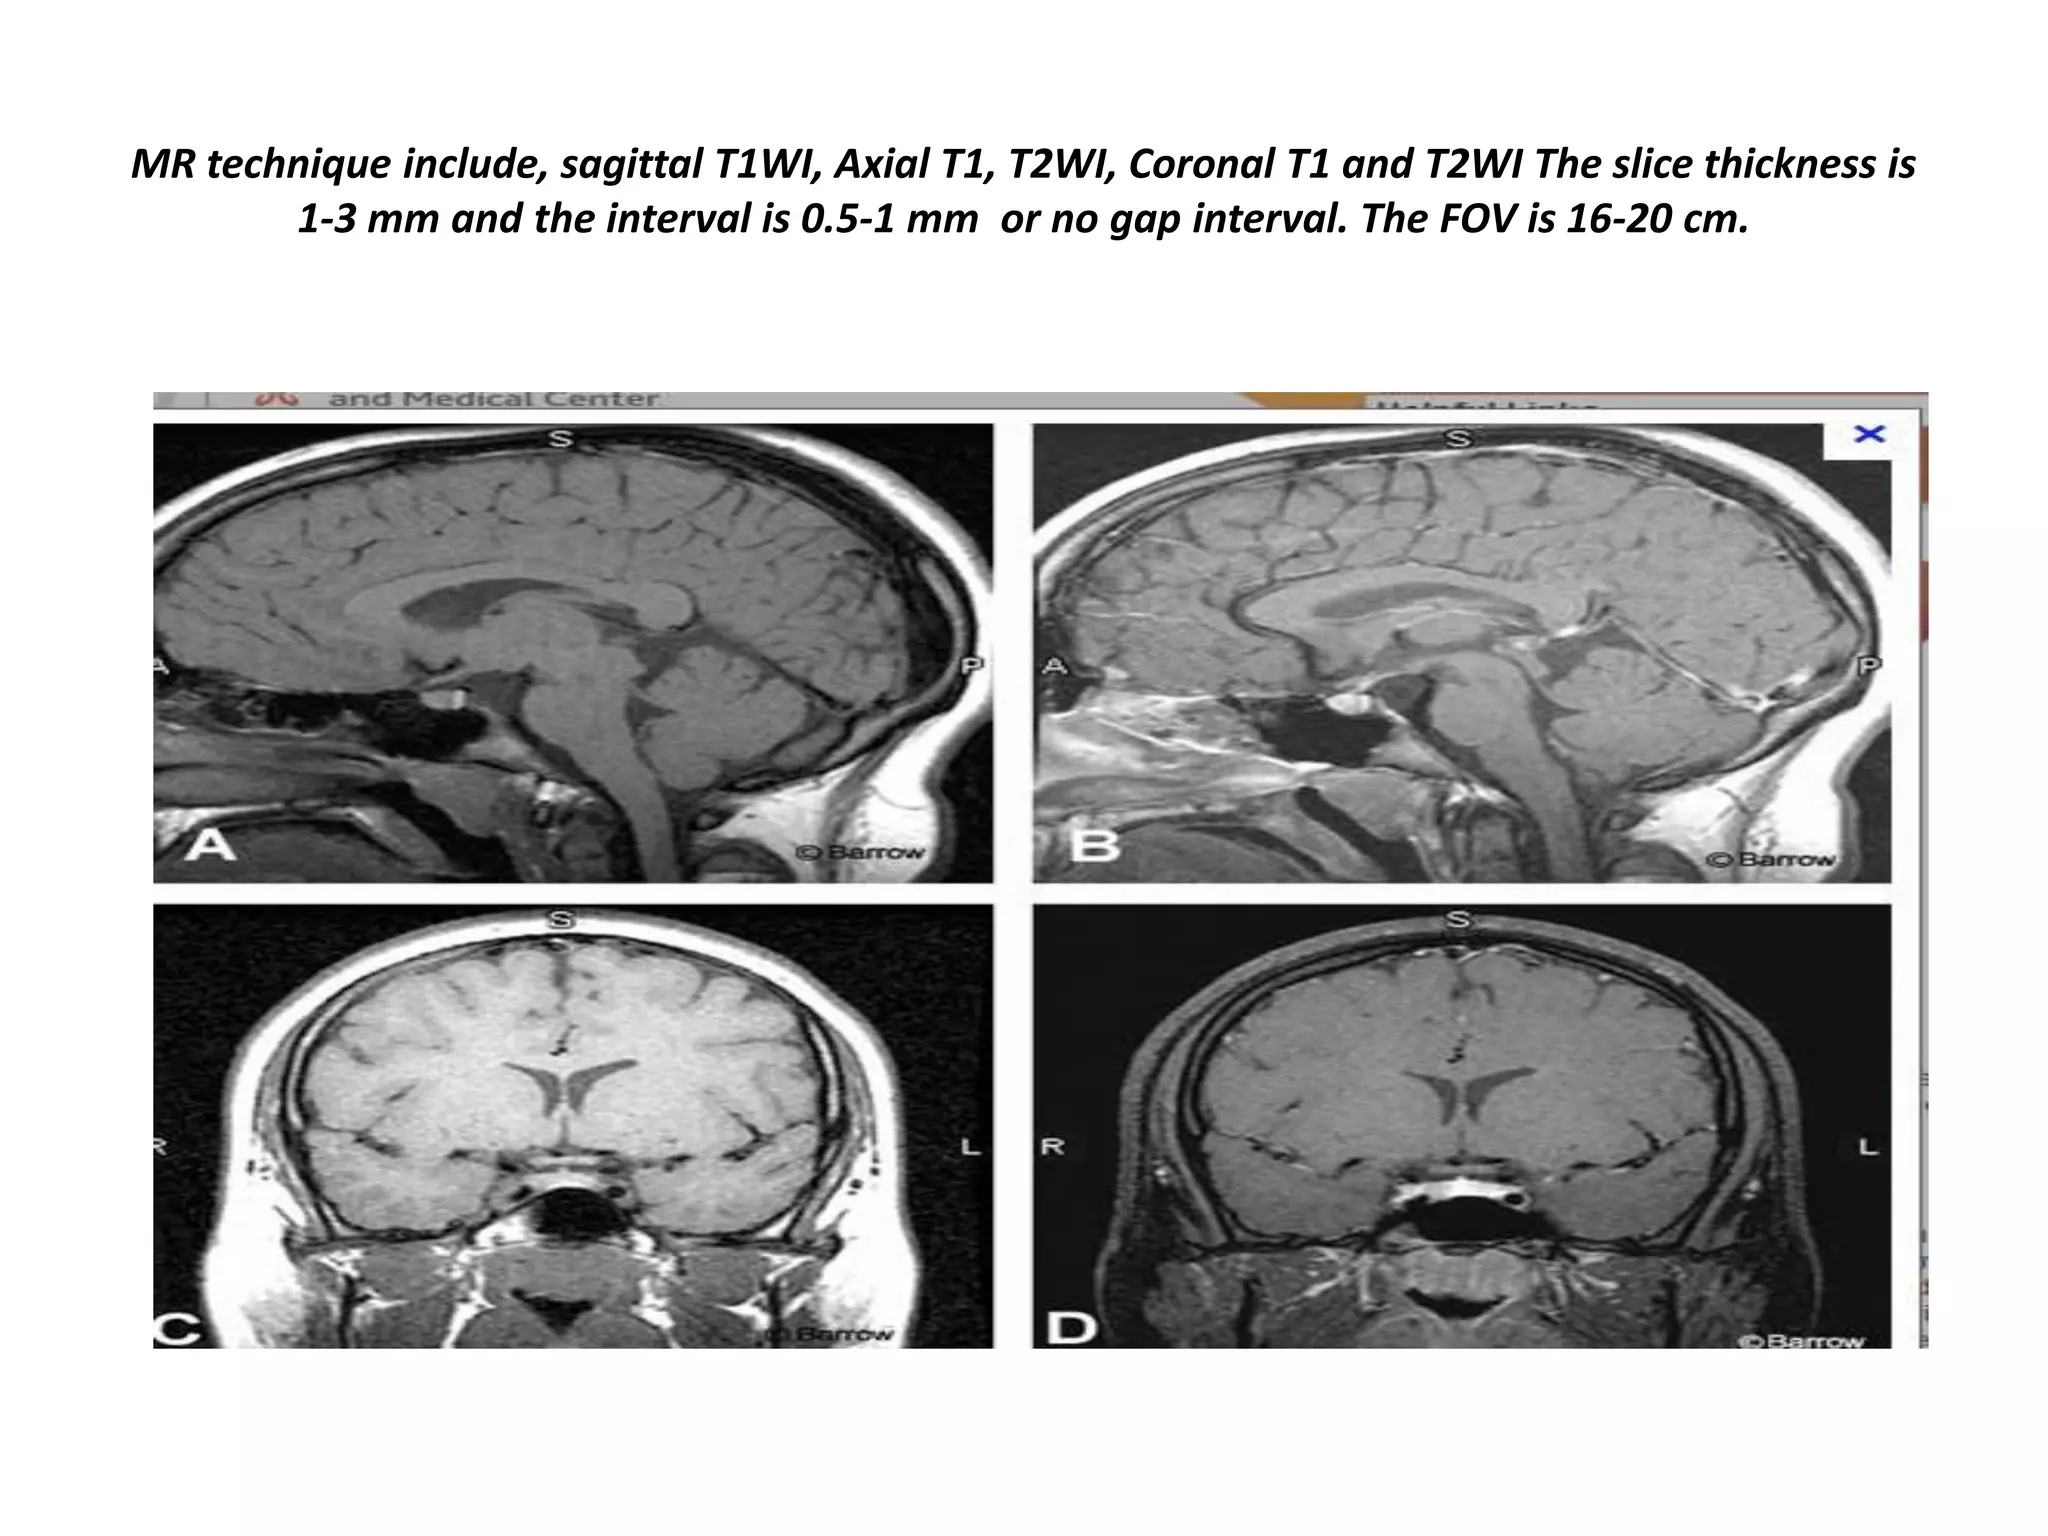

MR technique include, sagittal T1WI, Axial T1, T2WI, Coronal T1 and T2WI The slice thickness is

1-3 mm and the interval is 0.5-1 mm or no gap interval. The FOV is 16-20 cm.

MR technique include,sagittal T1WI, Axial T1, T2WI, Coronal T1 and T2WI The slice thickness is 1-3 mm and the interval is 0.5-1 mm or no gap interval. The FOV is 16-20 cm.